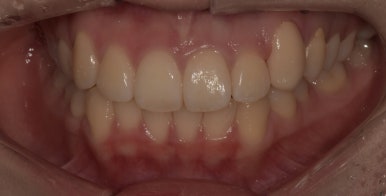

라미네이트 치료 전

2024-01-17

자, 먼저 이번 사례 환자분의 라미네이트 치료 전 사진을 먼저 보여드리겠습니다.

환자분은 다른 치아들은 비교적 가지런한 편인데 왼쪽 3번째 송곳니 (사진상 오른쪽)

#23 치아가 다소 뻐드러져있는 상태였습니다.

그래서 최대한 이 치아를 가지런하게 정돈하는 것을 목표로 치아 1개만 라미네이트 치료를 하기로 했고요.